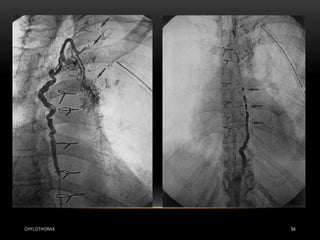

• Today there are several radiological treatments that can be used

in both traumatic and non-traumatic chylothorax .

• Much more experience is available for percutaneous

embolization of the thoracic duct , which can be performed as

an alternative to thoracic duct ligation and can be performed in

both adults and children .

• Embolization has a much higher success rate: if the thoracic

duct can be intubated successfully, the procedure is successful

in well over 90% of cases

CHYLOTHORAX 54

INTERVENTIONAL RADIOLOGY CHYLOTHORAX 53 •Today there are several radiological treatments that can be used in both traumatic and non-traumatic chylothorax . • Much more experience is available for percutaneous embolization of the thoracic duct , which can be performed as an alternative to thoracic duct ligation and can be performed in both adults and children . • Embolization has a much higher success rate: if the thoracic duct can be intubated successfully, the procedure is successful in well over 90% of cases